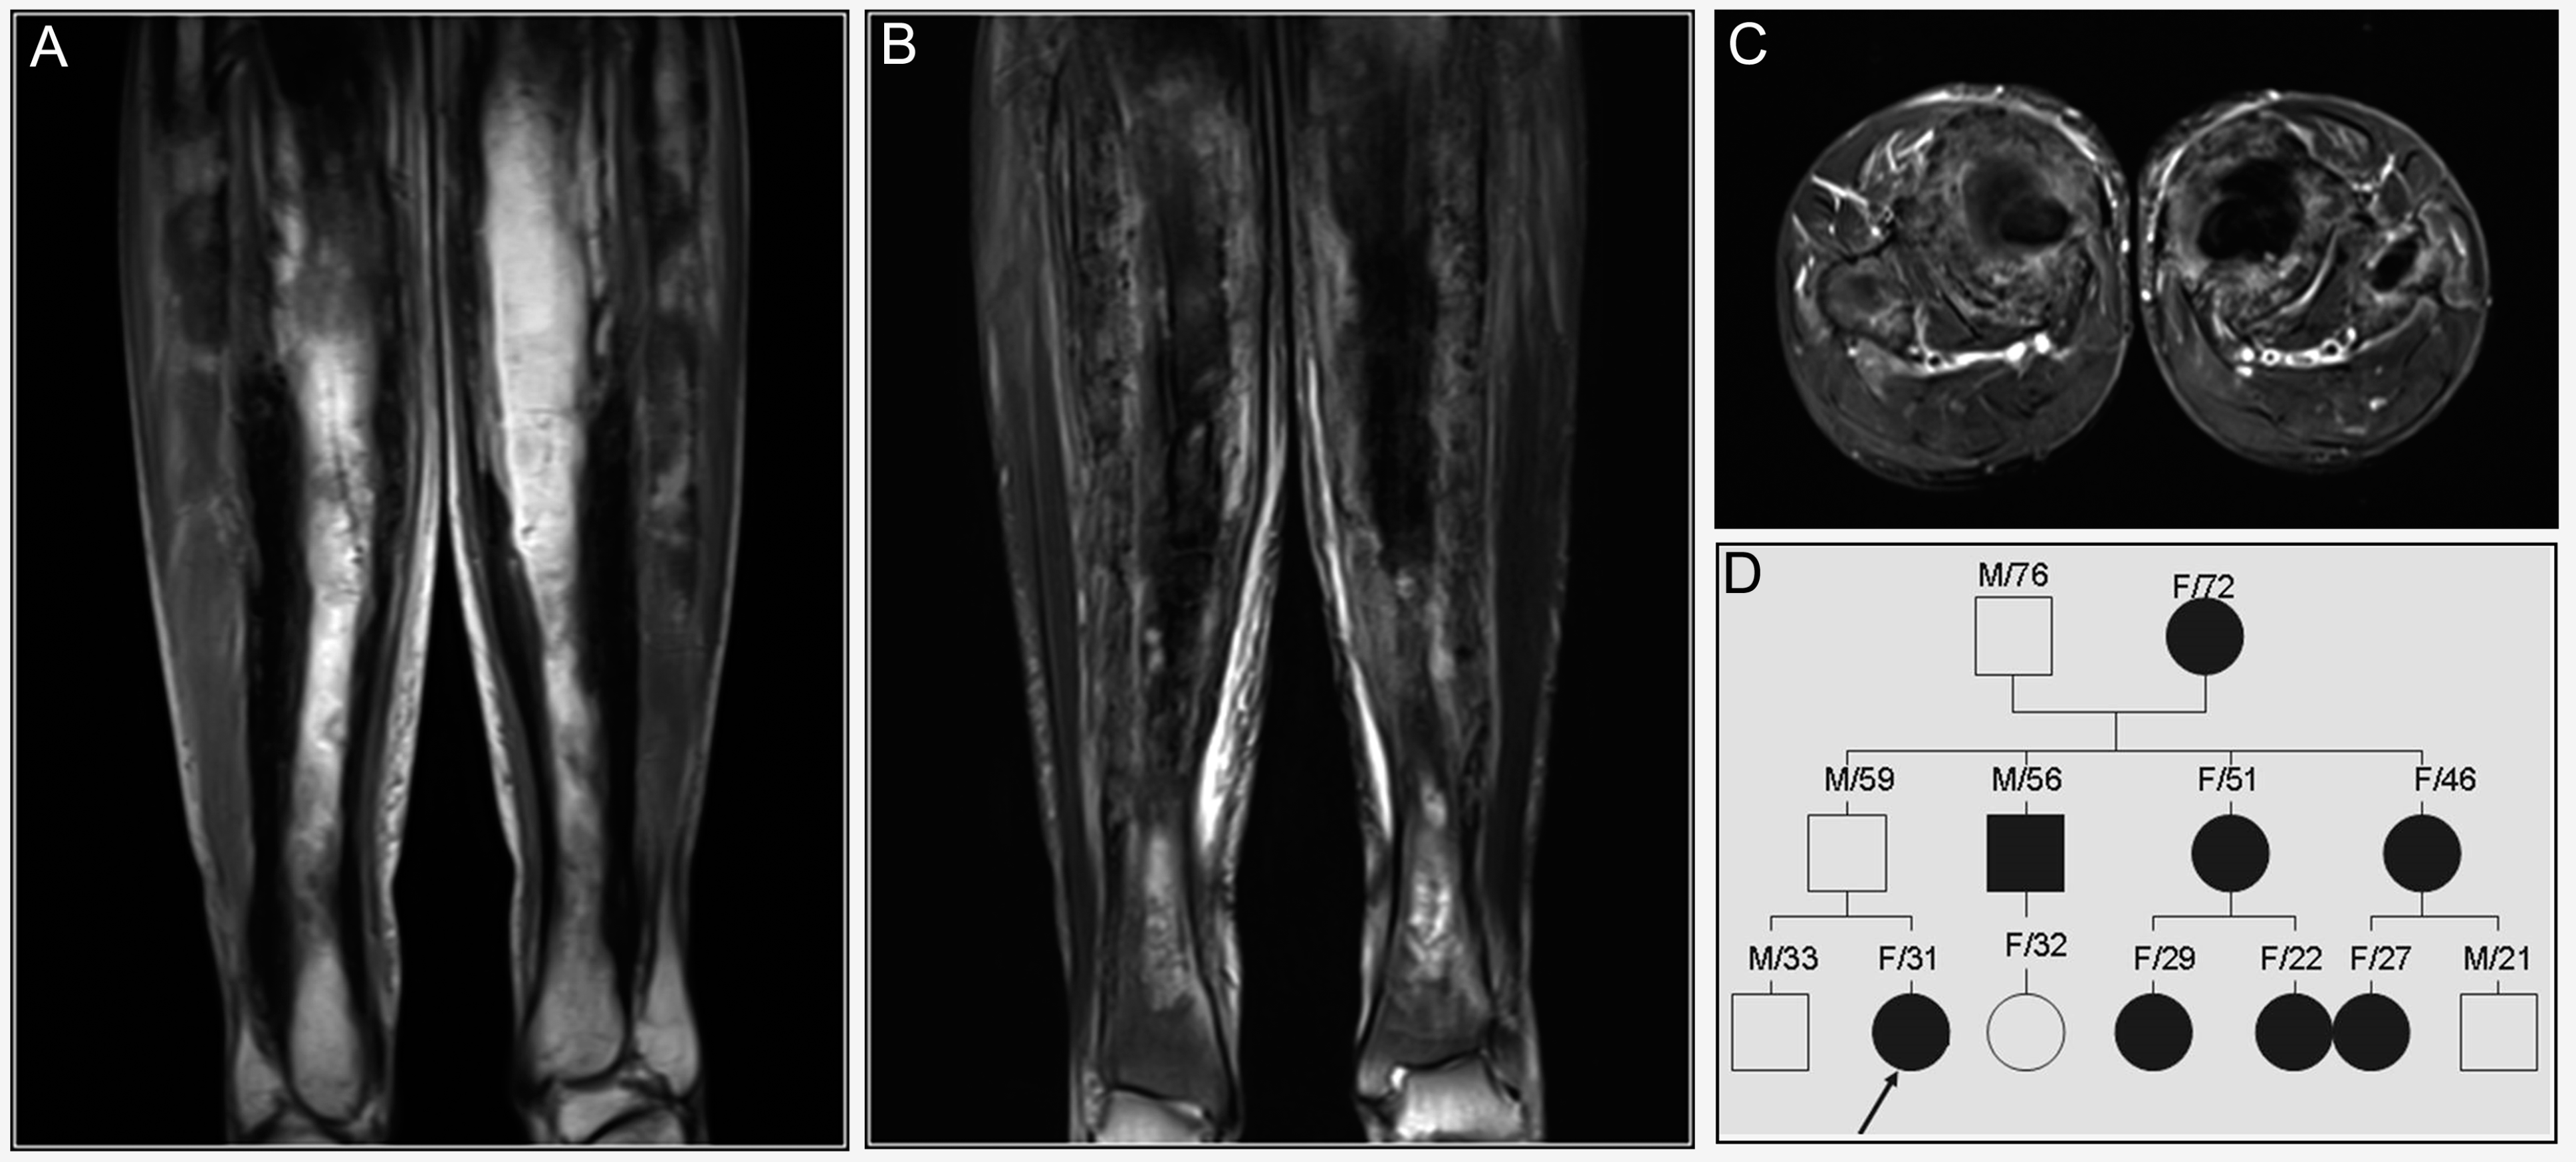

3.2. Gaucher’s Disease (GD)

3.6. Langerhans Cell Sarcoma